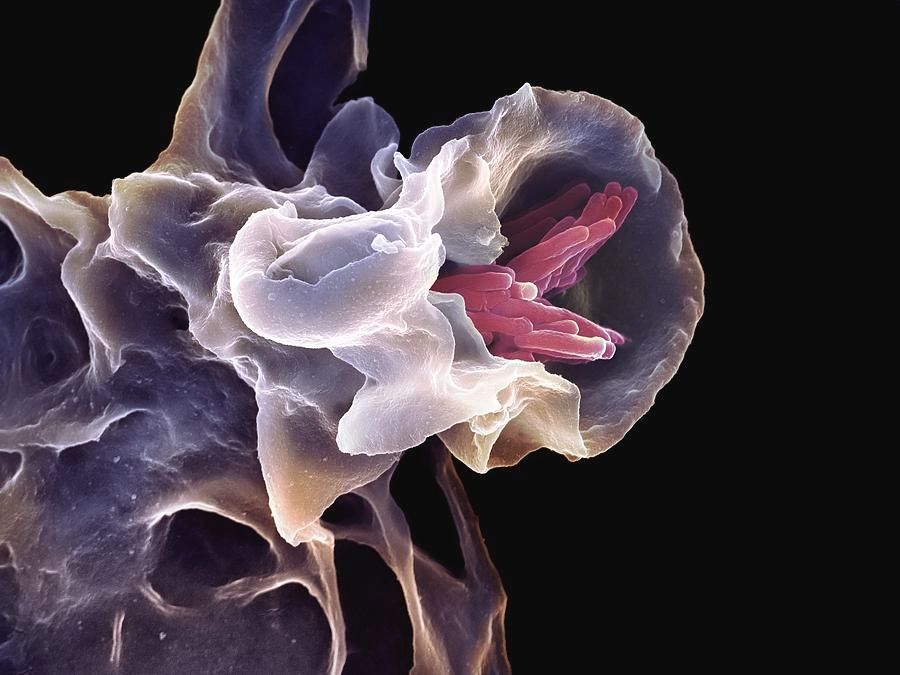

The most well-known method by which tuberculosis manipulates our immune system is through macrophages. They are the primary defense against invaders, the clean-up crew, and the primary tuberculosis target. The bacterium prefers to be engulfed by lung macrophages, which create a dense clump of cells that hides the bacterium for a long time, sometimes even years.